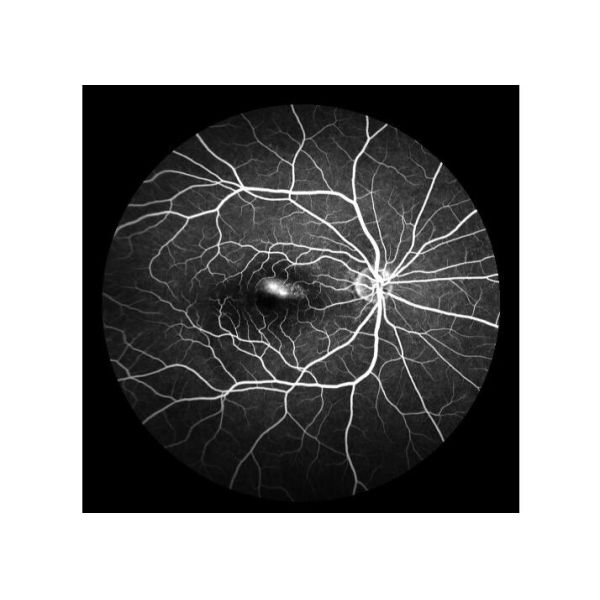

| 1 |  | Fundus Fluorescein Angiography(FFA): Retinal circulatory change | 1) ”Golden standard” to judge retina disease 2) To reflect the physiological pathology of retinal blood vessels to capillaries 3) To comprehensively inspect diseases undetected in normal fundus examination |

| 2 |  | Indocyanine Green Angiography(ICGA) Choroid vessels and RPE lesions | 1) Golden standard for PVC diagnosis 2) To reveal the details of the choroid cycle 3) Supplement to FFA,to find latent CNV undetected on FFA 4) Mainly to reflect blood vessels condition in early and middle stage, in late stage to reflect the form and function of RPE cells |

Cases

Retina Angiograph Digital 160° Ophthalmic Equipment Images |